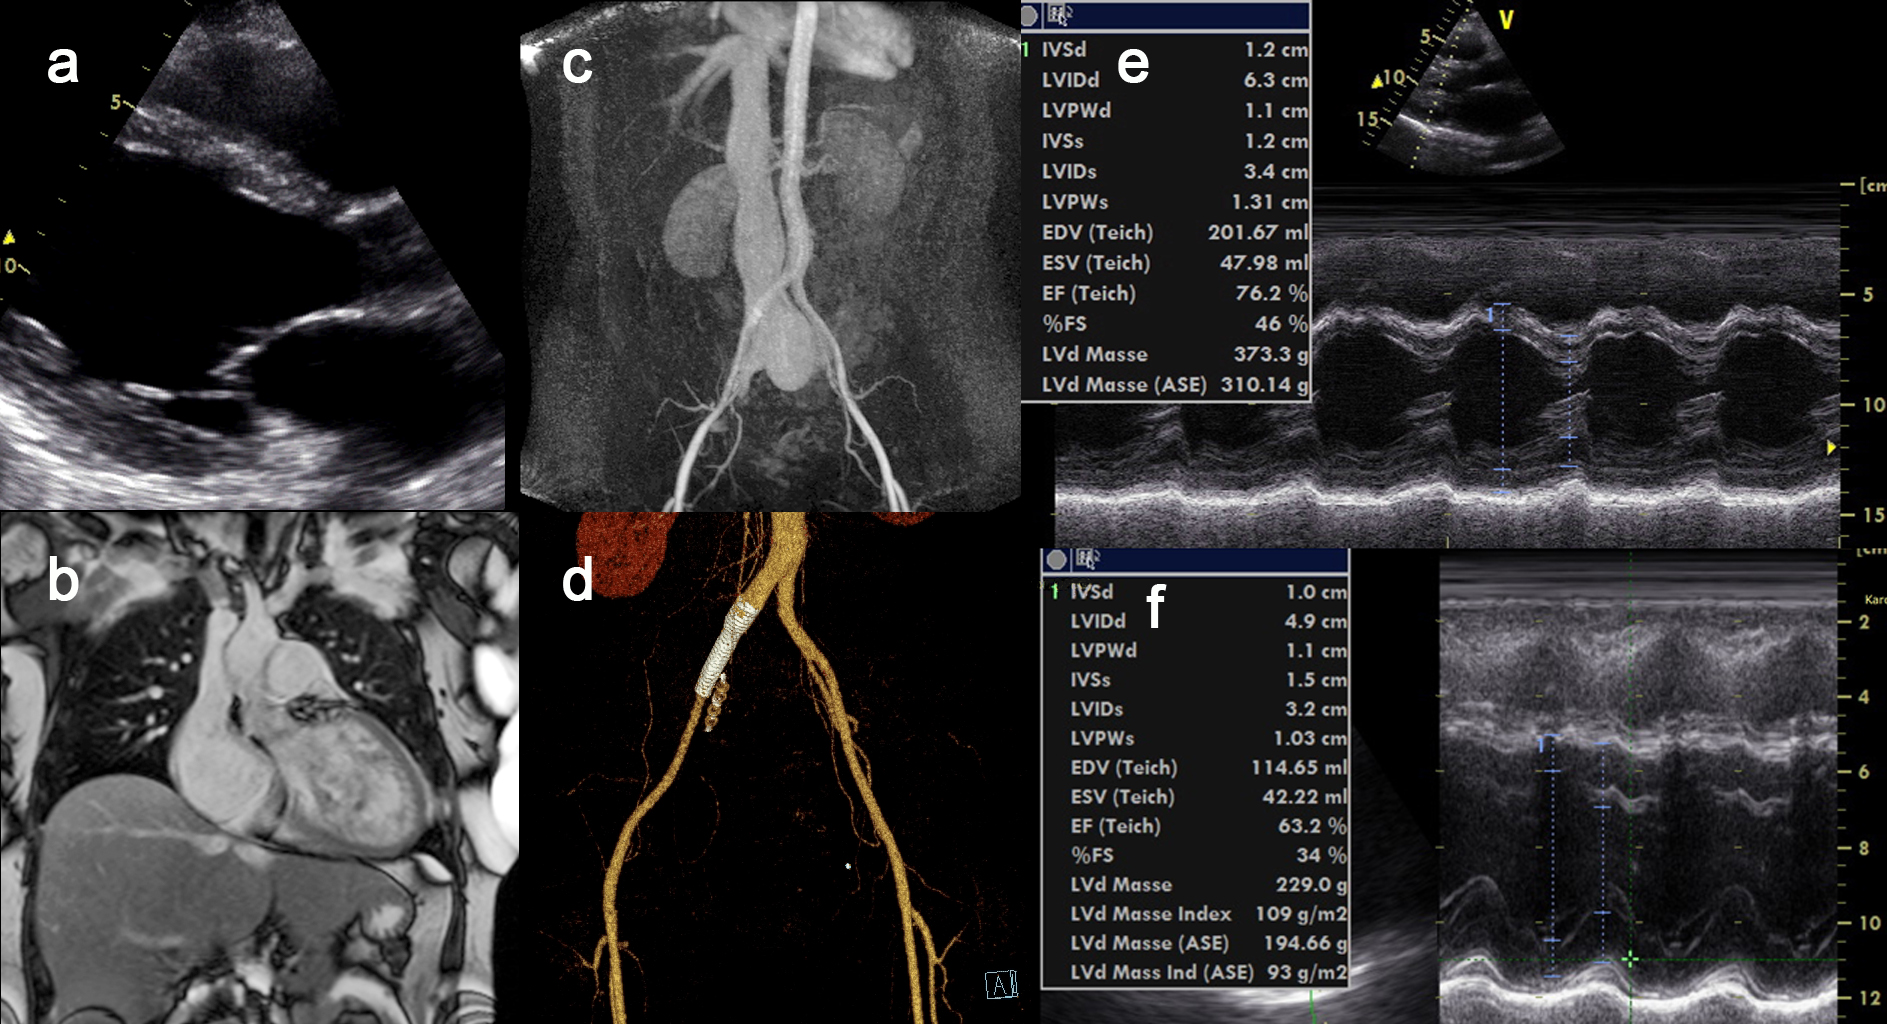

Examination Findings:On physical examination, a grade 3/6 systolic murmur was heard at Erb’s point; there was no peripheral edema, and blood pressure was 140/60 mmHg. Laboratory testing revealed a mildly elevated BNP, with no anemia or thyroid dysfunction. Resting ECG showed sinus rhythm at 93 bpm with P mitrale and a positive Sokolow–Lyon index. Echocardiography demonstrated enlargement of all four cardiac chambers (LV 68/42 mm; Fig. 1a, 1e), increased transvalvular flow velocities (aortic 2.6 m/s), an estimated systolic pulmonary artery pressure of 55 mmHg, and a markedly dilated inferior vena cava (4.5 cm).

Cardiac magnetic resonance imaging (MRI) confirmed a 30% increase in total heart volume (1150 mL) with no late gadolinium enhancement (Fig. 1b). Flow measurements over aorta and pulmonary artery were equal.

Given the high oxygen saturation in the inferior vena cava and the low diastolic pressure, abdominal MRI was performed, revealing a high-flow fistula between the right iliac artery and vein (Fig. 1c).

Therapy:Via the left femoral artery, the right internal iliac artery was initially occluded using two 8 mm Amplatzer Vascular Plugs IV (crossover technique) to prevent a type II endoleak. Subsequently, through the right femoral artery, the arteriovenous fistula was closed with two overlapping covered stents. Follow-up CT after four weeks confirmed complete occlusion of the fistula (Fig. 1d).

Discussion:Iliac arteriovenous fistulas are rare. They typically with aortic aneurysms or after lumbar disc surgery. Diagnosis is often delayed, and the resulting shunt may cause high-output heart failure. Endovascular closure with covered stents represents the treatment of choice and can be performed safely even in emergency situations. In this patient, interventional closure resulted in rapid clinical improvement with normalization of diastolic blood pressure and reduced heart rate. On echocardiographic follow up after four years a normalisation of cardiac output (aortic flow velocity 1,2 m/s) and regression of chamber dilatation (LV 49/32 mm, Fig 1f) could be documented. This case demonstrates the complete recovery from heart failure after treatment of the underlying shunt fistula.

Figure 1: Complete normalisation of cardiac function in high volume heart failure after closure Iliac arteriovenous fistula